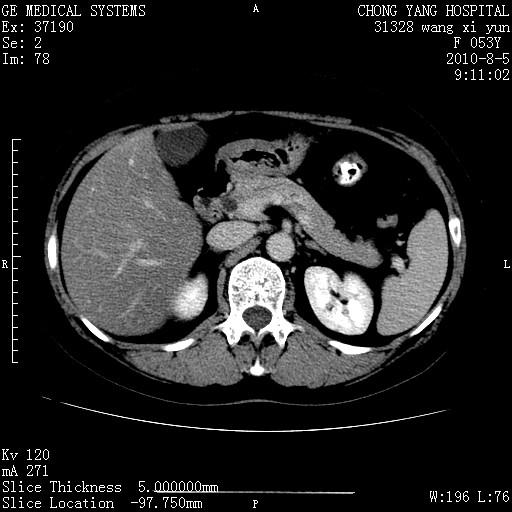

标题: CT28214:F41Y 血尿二十天,建议盆腔平扫加增强。

1)考虑肝左叶胆管细胞癌。2)脂肪肝。